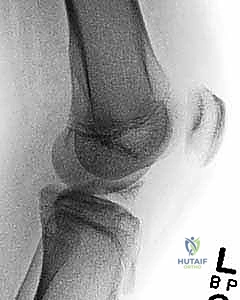

2. التصوير بالأشعة السينية (X-rays)

هي الخطوة الأولى والأساسية. يطلب الدكتور هطيف صوراً بأوضاع متعددة:

* صورة أمامية خلفية (AP): لرؤية الهيكل العام.

* صورة جانبية (Lateral): وهي الأهم لرؤية شوكة الظنبوب وتقييم درجة ارتفاعها وإزاحتها (لتحديد تصنيف مايرز ومكيفير).

* صورة النفق (Tunnel View): لرؤية الشق بين اللقمتين بوضوح.